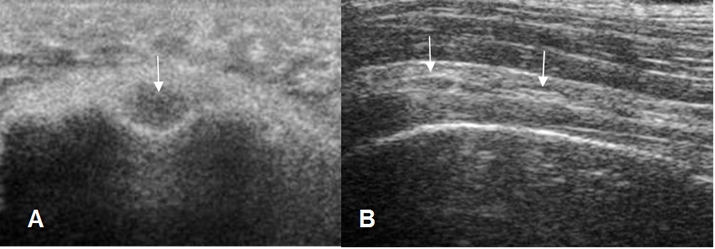

Fig 8. Tendón de la cabeza larga del biceps normal.

A: Ecografía axial y B: Ecografía sagital.